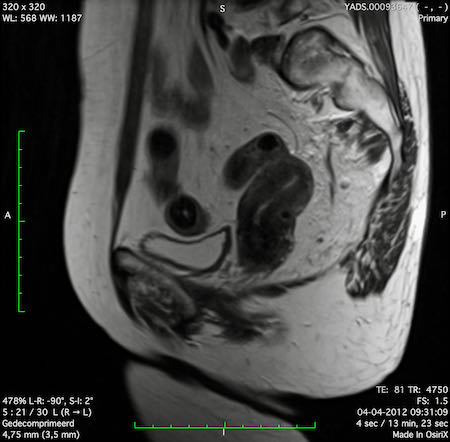

Hình ảnh

Các hình ảnh được cung cấp cho thấy ung thư biểu mô tế bào nhẫn với tình trạng dày lan tỏa thành trực tràng, hình ảnh bia bắn điển hình, và sự xâm lấn mỡ mạc treo trực tràng.